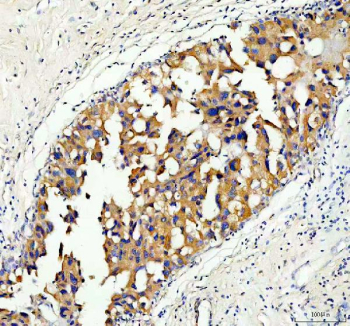

Immunohistochemical staining of Serine racemase using anti-Serine racemase antibody. Serine racemase was detected in a paraffin-embedded section of human breast cancer tissue. Heat mediated antigen retrieval was performed in EDTA buffer (pH 8.0, epitope retrieval solution). The tissue section was blocked with 10% goat serum. The tissue section was then incubated with 2 ug/ml rabbit anti-Serine racemase antibody overnight at 4oC. Peroxidase Conjugated Goat Anti-rabbit IgG was used as secondary antibody and incubated for 30 minutes at 37oC. The tissue section was developed using an HRP secondary and DAB substrate.